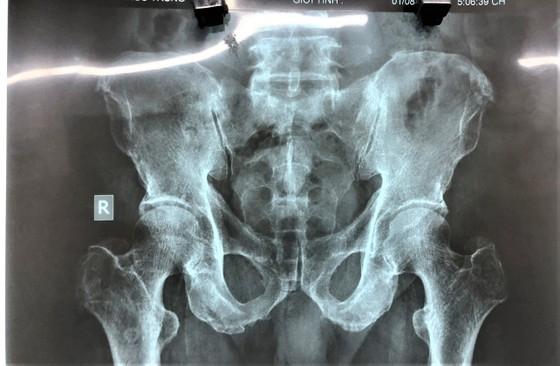

Dị vật qua chụp X-quang nằm sâu bên trong hậu môn bệnh nhân T.

Kết quả chụp X-quang xác định dị vật nằm sâu trong lòng trực tràng. Dị vật là một trái bí đao có kích thước 6x10cm. Các bác sĩ nội soi đã hội chẩn cùng Khoa Ngoại. Sau đó, nội soi trực tràng, nong hậu môn, dùng kẹp có móc, kẹp chặt nhẹ nhàng, xoay vòng và kéo dị vật ra ngoài thành công.

Dị vật trong hậu môn của bệnh nhân T. là trái bí đao, kích cỡ 6cmx10cm